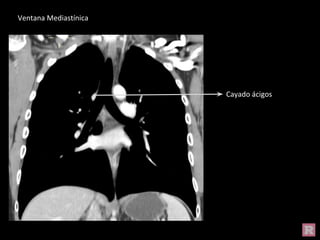

Ventana Pulmonar

Cayado ácigos